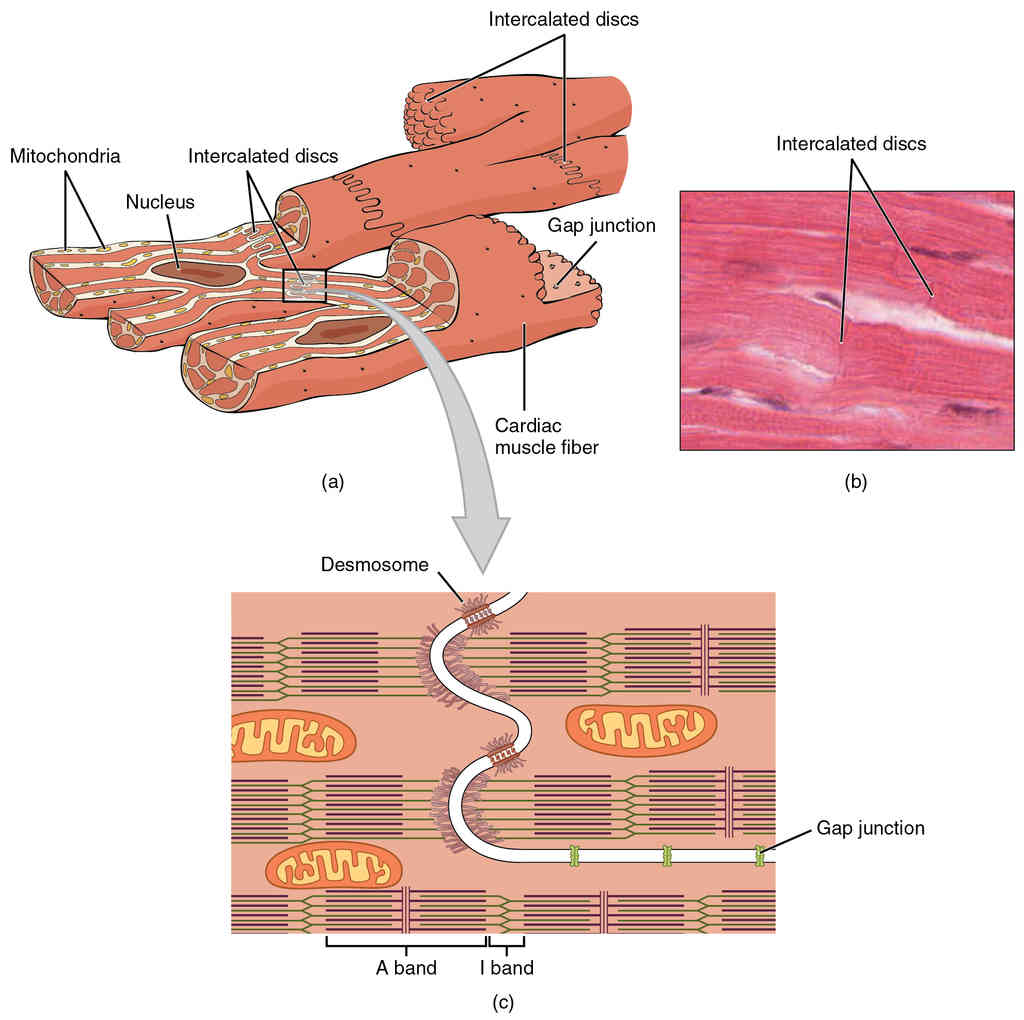

This page is under construction. For now, it is just a resource of the images found in the OpenStax Anatomy and Physiology Handbook. It wil slowly change into a revision tool. Each slide has a number. Use this to refer to the slide. When completed, it will have an unlabelled section, with labelled slides in parallel. On the unlabelled slides, write your answer and use the labelled slide to assess yourself. Keep track by also noting the number on each slide. Improvement at each attempt is important, more so than full marks on a first attempt.